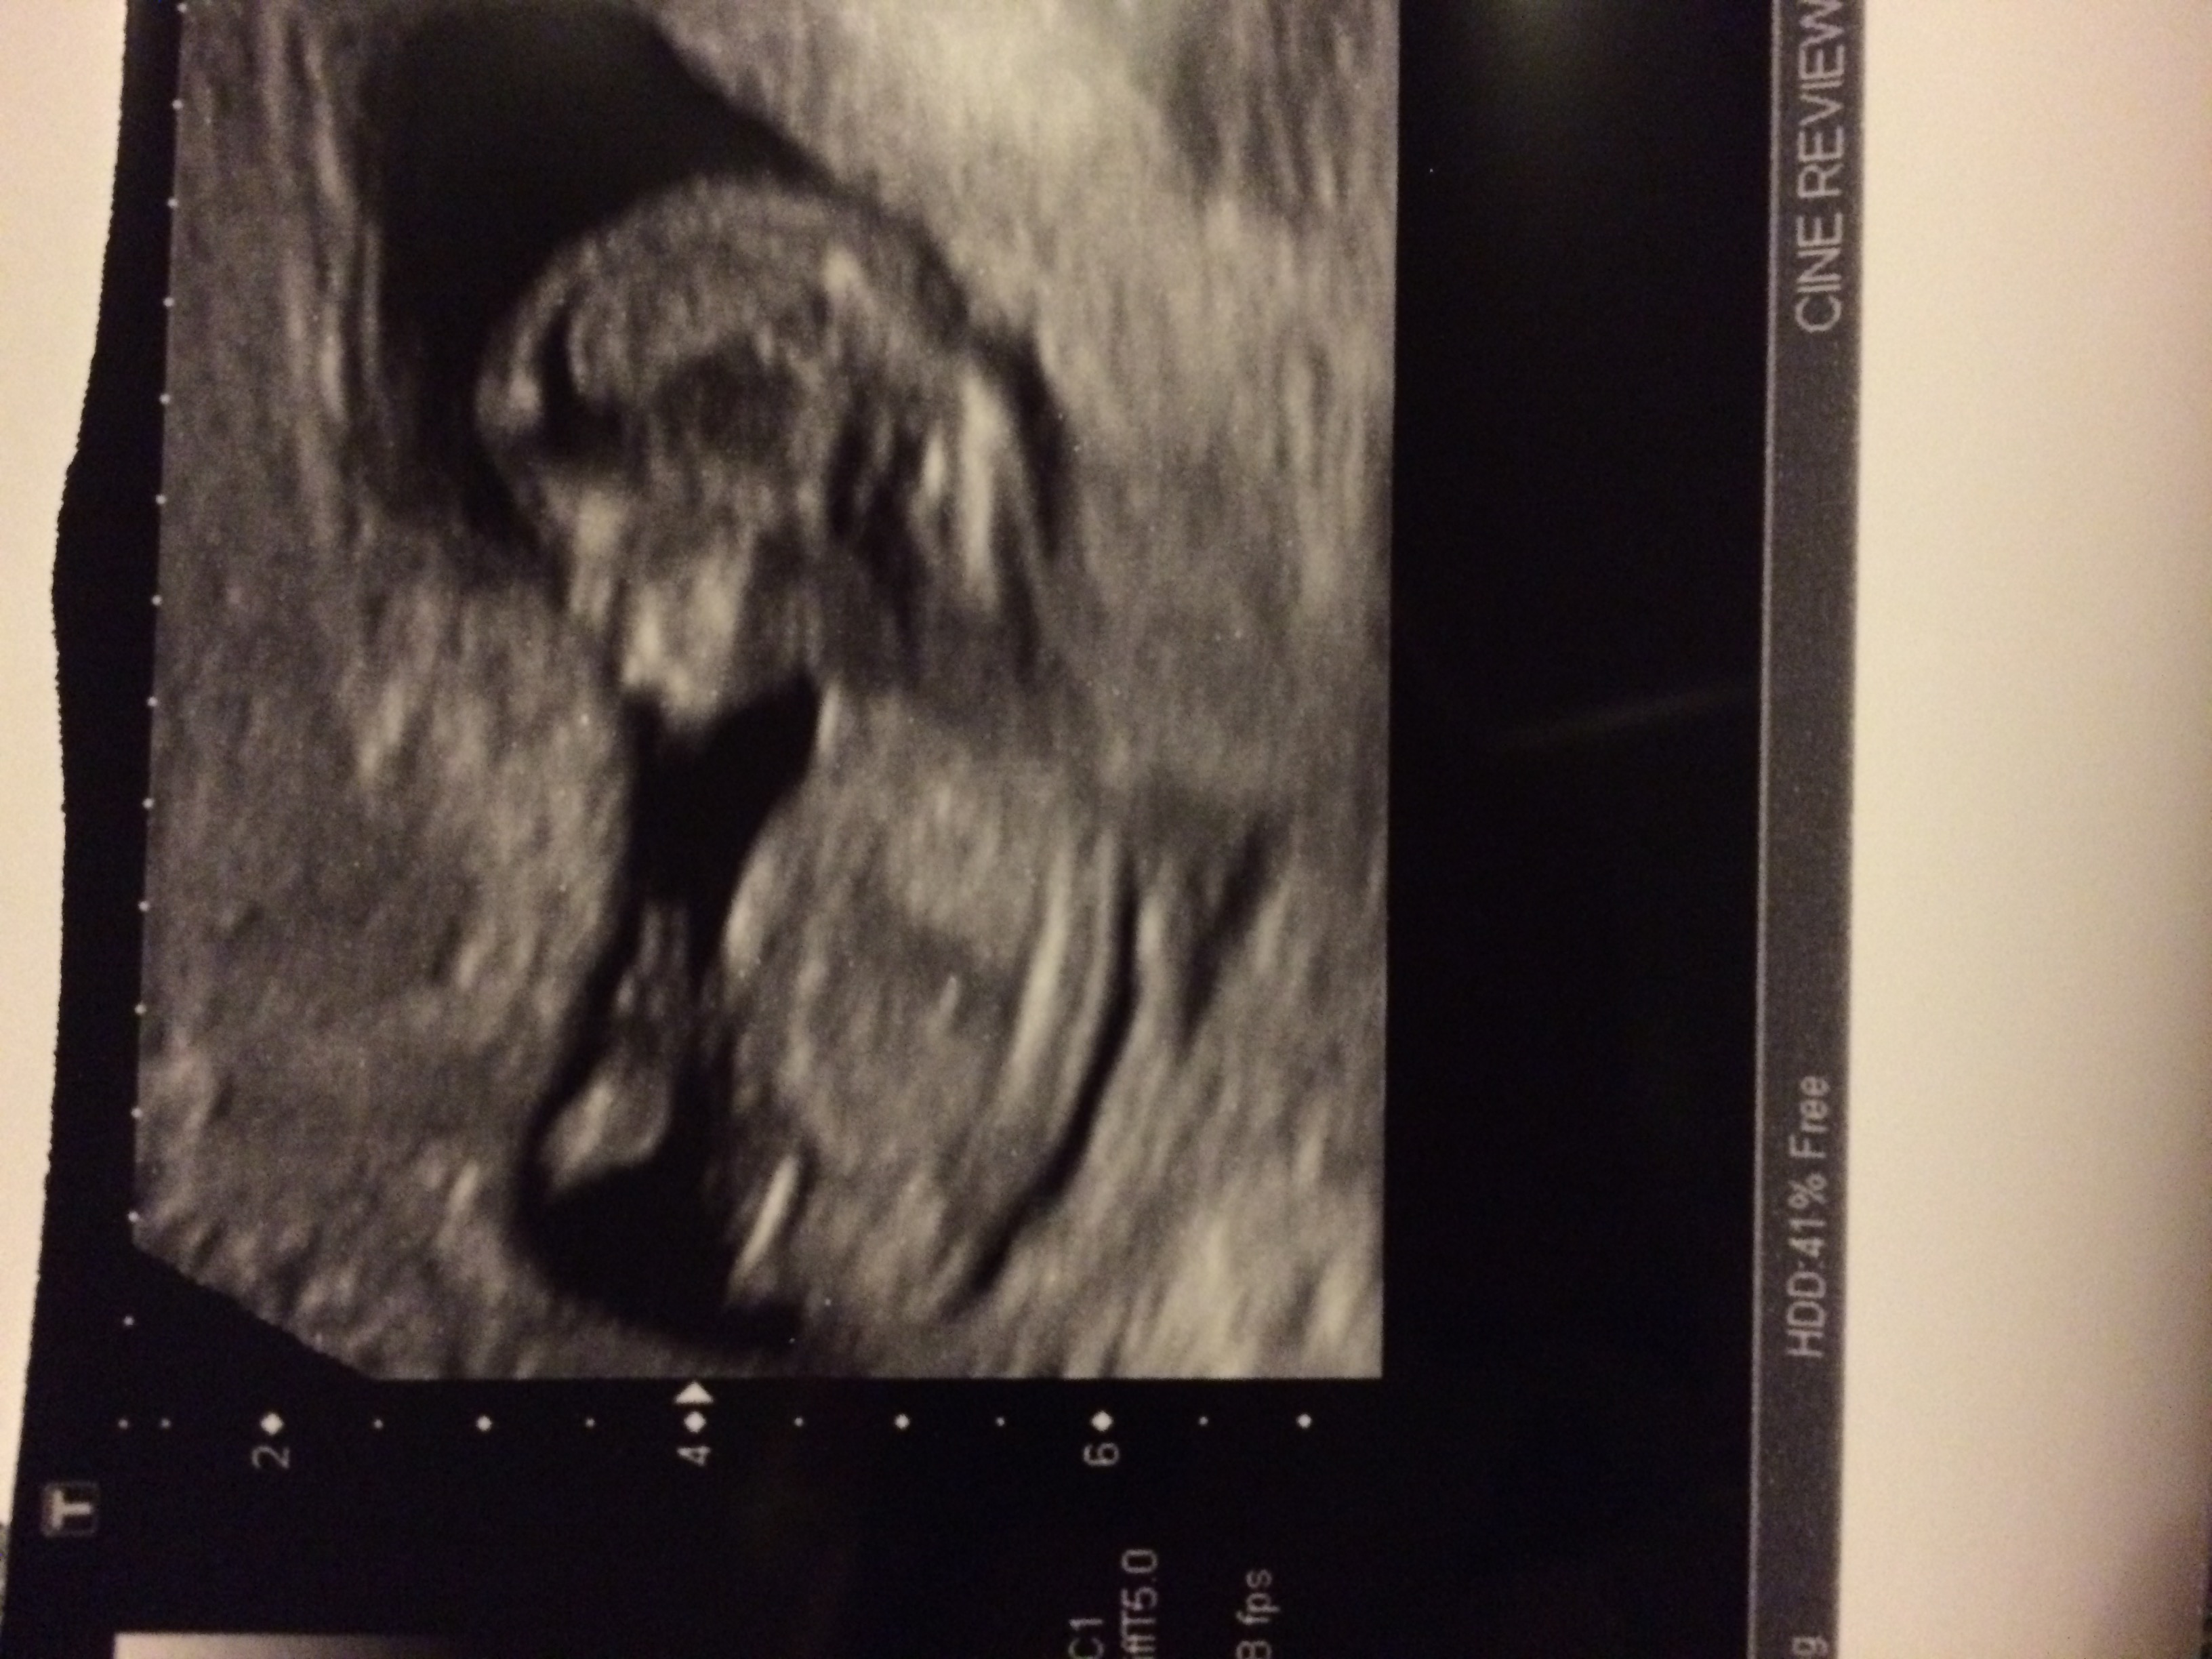

Attachment 28759

Just discovered this pic tucked behind the others, any clearer on here? Thanks in advance.